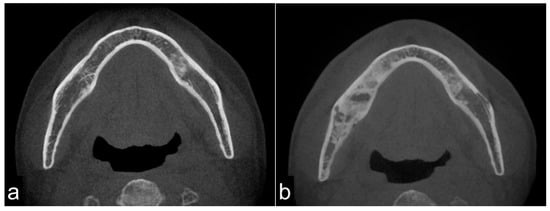

The schematic sequential mechanism of bone reaction after RT is shown in Figure 5.

Figure 5.

Schematic illustration of the progression of ORN. After radiation therapy, bone cells are damaged, leading to bone sclerosis (a). After that, the necrotic bone part is exposed (b). Stimulation such as tooth extraction causes infection and resorption of necrotic bone (c). When the cortical bone ruptures, inflammation spreads to the surrounding soft tissue, resulting in trismus (d). Eventually, it causes a pathological fracture.